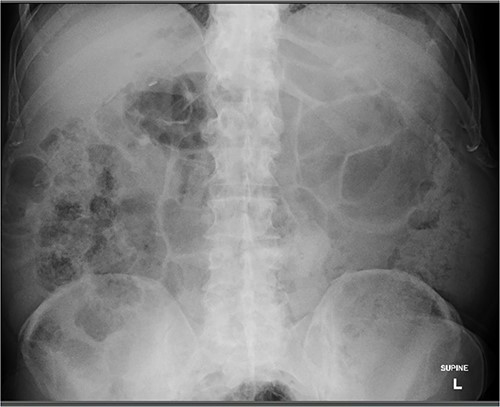

An 80 year old male presented to the emergency department after accidentally swallowing his hearing aids. On presentation he was pain free, hemodynamically stable, and had a soft abdomen. He had a background of type-2 diabetes, rheumatoid arthritis and diverticulitis. The hearing aids were powered by lithium battery. X-ray found two foreign bodies in the left upper abdomen (Fig. 1). After assessment in the emergency department, he returned home to await their natural passage. One hearing aid was found in his stools the following day, but he represented three weeks later as the second hearing aid remained unaccounted for. He underwent repeat abdominal x-ray and CT, which found the hearing aid retained within a presumed distal duodenal diverticulum (Figs 2 and 3). He was booked a push enteroscopy the following day.

Abdominal X-ray identifying two hearing aids on day of initial presentation.